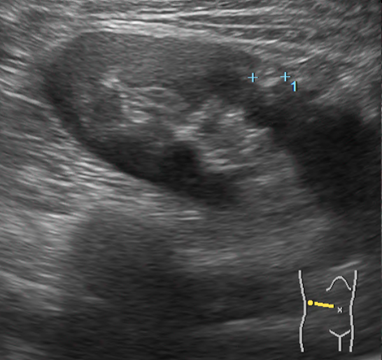

보통 초음파 검사에서 신장 혈관근지방종이 자주 발견됩니다. 초음파 상에서 이 종양은 주위 조직과 경계가 뚜렷하며, 밝은 흰색으로 보이는데, 이는 지방 조직이 초음파에 밝게 나타나기 때문입니다. 더불어 내부 혈관 구조가 관찰되는 경우도 있습니다.